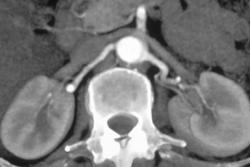

Renal Carcinoma